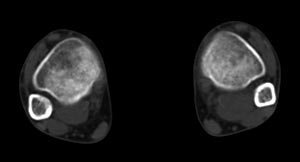

x线检查月前片示双踝关节骨质未见明显异常。一月后肿胀大部消失,疼痛稍有好转,摄片示两侧骨下段条带状高密度影,边界尚清。ct扫描示两侧胫骨下段骨皮质增厚不明显,髓腔内密度显示磨玻璃样增高,髓腔显示狭窄。

x线检查一个月前示双踝关节骨质未见异常。一个月后肿胀大部消失,疼痛稍有好转,摄片示两侧胫骨下段横行条状高密度影,边界较清。ct扫描示:两侧胫骨下段未见骨皮质增厚,两胫骨下段近骨端处可见骨小梁增粗但纹理尚清晰,未见明显骨质破坏,邻近关节及关节囊未见明显异常,软组织内未见异常.综上所诉考虑1.低毒感染所致,2.假性痛风

x线片表现为双侧胫骨下端粗条状磨玻璃样增高密度影,并可见骨皮质稍不连续。ct表现为双侧胫骨下端髓腔内磨玻璃样增高密度影,未见明显骨皮质不连续(可能与扫描体位有关)。

本例应该考虑为双侧胫骨下端应力性骨折。